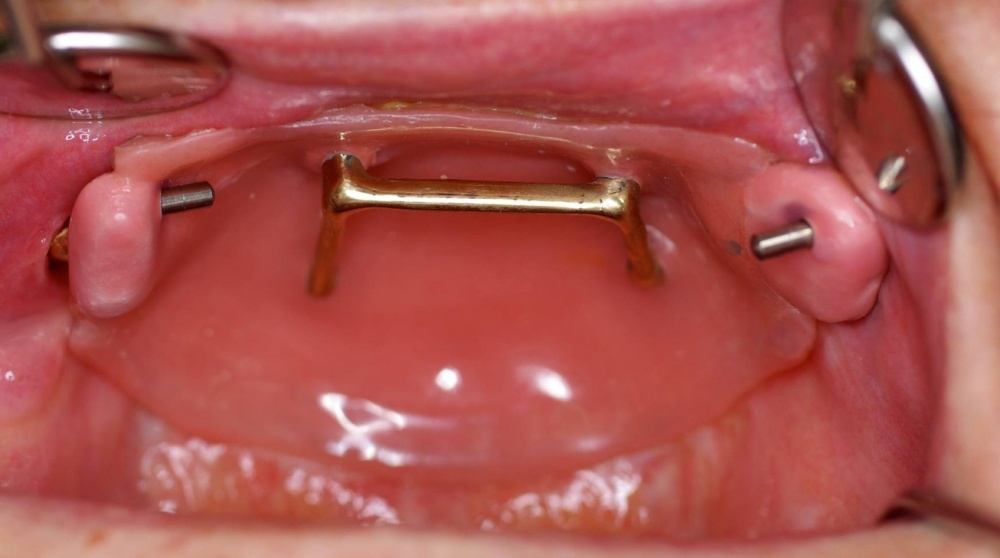

Die Behandlung Schlafbezogener Atmungsstörungen (SBAS) stellt ein klassisches Beispiel der interdisziplinären Zusammenarbeit dar, können hierbei doch mehrere verschiedene Fachrichtungen beteiligt sein. Schlafbezogene Atmungsstörungen entstehen durch eine Verengung der oberen Atemwege, die bis zum kompletten Verschluss gehen kann (Abb. 3). Sie weisen eine hohe Prävalenz auf, so leiden etwa 40 % der vierzigjährigen männlichen und 30% der gleichaltrigen weiblichen Bevölkerung in Deutschland an Primärem Schnarchen, mit zunehmendem Lebensalter nimmt die Prävalenz weiter zu. An dem Obstruktiven Schlafapnoe Syndrom (OSAS) leiden etwa 4 % der Gesamtbevölkerung, wobei Männer im Verhältnis von neun zu vier häufiger als Frauen betroffen sind, der Altersgipfel liegt zwischen 40 und 60 Jahren. Schlafbezogene Atmungsstörungen sind gerade für die Soldaten der Bundeswehr von besonderem Interesse. Vor allem beim Obstruktiven Schlafapnoe Syndrom ist der Schlaf gravierend gestört, ein erholsamer Schlaf oft nicht mehr möglich. Auf alle daraus resultierenden, wissenschaftlich belegten Folgen kann hier nicht eingegangen werden, es sei jedoch beispielhaft auf die Tagesmüdigkeit und die reduzierte Leistungsfähigkeit verwiesen. Der Soldatenberuf ist jedoch vielfach mit hohen Anforderungen an die körperliche Leistungs- und Konzentrationsfähigkeit verbunden, sodass diesbezügliche Einbußen gravierende Einflüsse auf die Verwendungsfähigkeit haben können. Das Primäre Schnarchen hat zwar zunächst keine diesbezüglichen Folgen, hier sei jedoch an den kameradschaftlichen Frieden erinnert. Dieser kann durch das Schnarchen einzelner Kameraden beim Schlafen in Gemeinschaftsunterkünften (beispielsweise im Einsatz) erhebliche Störungen erfahren.

An der Behandlung schlafbezogener Atmungsstörungen können verschiedene Fachrichtungen beteiligt sein. Sie sind für den Zahnmediziner von besonderem Interesse, da sich durch zahnärztliche Einflussnahme auf die beteiligten oralen Strukturen mögliche zahnärztliche Therapieoptionen ergeben. Hierfür hat sich die Anwendung von Unterkieferprotrusionsschienen bewährt. Ihre Wirksamkeit konnte in einer Vielzahl von Studien belegt werden und ist bei entsprechenden Vorbefunden von den entsprechenden Fachgesellschaften allgemein anerkannt. Die Behandlung einer schlafbezogenen Atmungsstörung darf nie durch einen Zahnmediziner alleine erfolgen. Auch wenn vom Zahnarzt zunächst nur die Diagnose Primäres Schnarchen vermutet wird, muss der Patient an einen Schlafmediziner zur Diagnosestellung überwiesen werden. Gemäß der geltenden Gesetzeslage und den geltenden Leitlinien ist der Zahnmediziner nicht befugt, eine Schlafbezogene Atmungsstörung zu diagnostizieren. In diesem Zusammenhang sei ausdrücklich auf mögliche rechtliche Konsequenzen, z. B. nach einem Verkehrsunfall aufgrund eines unzureichend behandelten OSAS, verwiesen. Hinter jedem Schnarcher kann sich ein Patient mit einem OSAS verbergen. Im Idealfall werden die Patienten von einem Schlafmediziner voruntersucht an den Zahnmediziner überwiesen. Schlafmediziner können Internisten/Pneumologen, Hals-Nasen-Ohrenärzte, Kardiologen, Psychiater oder auch entsprechend fortgebildete Kollegen anderer medizinischer Fachrichtungen sein. Bei dem nicht entsprechend voruntersuchten Patienten können verschiedene Symptome bzw. klinische Befunde den Verdacht auf eine Schlafbezogene Atmungsstörung nahelegen. Hat der Zahnarzt aufgrund verschiedener Symptome den Verdacht auf eine Schlafbezogene Atmungsstörung und der Patient ist noch nicht entsprechend voruntersucht, überweist er den Patienten zunächst an einen Schlafmediziner der genannten Fachrichtungen. Dieser führt die entsprechende Diagnostik durch. Dazu stehen grundsätzlich die Polygraphie und die Polysomnographie zur Verfügung. Im Bundeswehrkrankenhaus Hamburg wird die interdisziplinäre Schlafsprechstunde federführend von der Neurologie (Abt. VIa) durchgeführt, dort besteht auch die Möglichkeit der Polysomnographie. Die Polygraphie erfolgt im Regelfall mittels portabler Geräte, die der Patient mit nach Hause nimmt und mit denen für mindestens 6 Stunden verschiedene Parameter erfasst werden; entsprechende Geräte werden u. a. in der Abteilung für Innere Medizin vorgehalten. Der Schlafmediziner entscheidet nach entsprechender Befundung und Diagnosestellung, ob die Anwendung einer Unterkieferprotrusionsschiene in Frage kommt und überweist gegebenenfalls zurück an den Zahnmediziner (Abb. 4). Hier sei ausdrücklich erwähnt, dass viele wichtige Aspekte zur Anwendung von Unterkieferprotrusionsschienen im Rahmen dieses Artikels nur kurz oder nicht erwähnt werden können. Dem interessierten Leser sei daher die weitergehende Lektüre zu diesem Thema empfohlen.